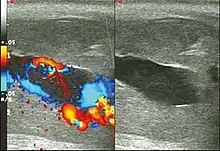

Ultrasonography

Color Doppler ultrasound demonstrating a hypoechoic collection that corresponds to hematoma with arteriovenous fistula secondary to traumatic injury of the penis due to impact with bicycle handlebars, resulting in high-flow priapism.[11]

Penile ultrasonography with Doppler is the imaging method of choice, because it is noninvasive, widely available, and highly sensitive. By means of this method, it is possible to diagnose priapism and differentiate between its low- and high-flow forms.[11]

In low-flow (ischemic) priapism the flow in the cavernous arteries is reduced or absent. As the condition progresses, there is an increase in echogenicity of the corpora cavernosa, attributed to tissue edema. Eventually, changes in the echotexture of the corpora cavernosa can be observed due to the fibrotic transformation generated by tissue anoxia.[11]

In high-flow priapism normal or increased, turbulent blood flow in the cavernous arteries is seen. The area surrounding the fistula presents a hypoechoic, irregular lesion in the cavernous tissue.[11]